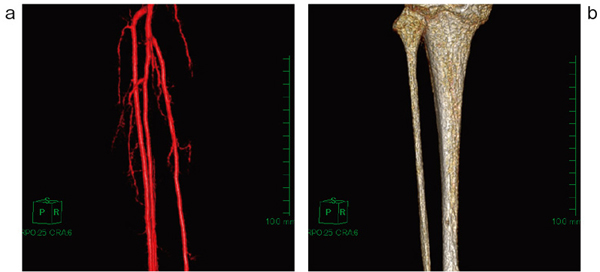

図6 症例2:下腿部動脈のVR像と骨のVR像

a:下腿部動脈のVR像 b:単純T1強調像の骨髄信号から作成した骨のVR像